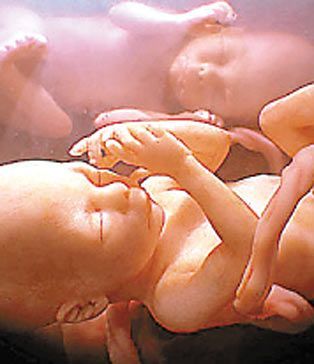

一对双胞胎姐妹中的一个斜靠在另一个身上,还亲了一下对方的脸——这个温馨的画面不是发生在某座大房子里,而是发生在妈妈的子宫里!在英国媒体日公布的一系列照片中,读者能够清晰地看到这些令人震惊的“四维”超声波图像,看到双胞胎和多胞胎是怎样在妈妈的子宫里“玩耍”的。

由于对胎儿进行的是实时拍摄,科学家把这些珍贵的图像称为“四维”图像,他们按照这些图像制作出真实大小的硅树脂模型,并用电脑制作出令人震惊的多胞胎图像。